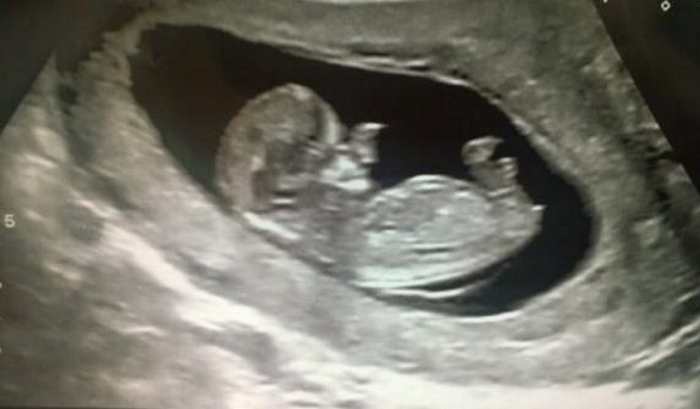

Sin embargo, en la semana 20 del embarazo, durante un ultrasonido, los médicos encontraron un tejido más suave creciendo alrededor de la nariz del pequeño bebé ¡Desde entonces, la mujer ya sabía que su hijo no nacido no sería como los demás!

Ollie, así se llamó el bebé, nació con una hernia cerebral, por la que parte del cerebro sobresalía por su nariz. Con el tiempo, el cerebro del bebé iría creciendo, y por lo tanto, acumulándose en la nariz.